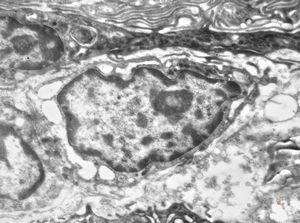

F,41y. | synovial metaplasia - capsule of implantate

F,41y. | synovial metaplasia - capsule of implantate

F,41y. | synovial metaplasia - capsule of implantate

F,41y. | synovial metaplasia - capsule of implantate

F,41y. | synovial metaplasia - capsule of implantate

F,41y. | synovial metaplasia - capsule of implantate

F,41y. | synovial metaplasia - capsule of implantate

F,41y. | synovial metaplasia - capsule of implantate

F,41y. | synovial metaplasia - capsule of implantate